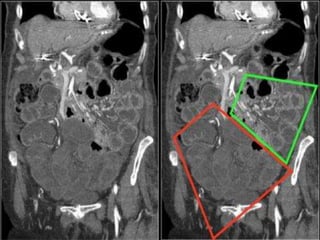

SMV THROMBOSIS

ARTERIAL OCLUSIVE ISCHEMIA VENOUS OCLUSIVE ISCHEMIA

SMA THROMBOSIS SMV THROMBOSIS

NO /SUBTLE BOWEL ENHANCEMENT HYPO/HYPERDENSE BOWEL WALL

THINNED BOWEL WALL (PAPER THIN

BOWEL )

SIGNIFICANT BOWEL WALL

THICKENING

NO MUCOSAL ENHANCEMENT MUCOSAL ENHANCEMENT

BOWEL LOOP DILATATION ONLY AFTER

INFARCTION

DILATED BOWEL LOOPS WITHOUT

LATE STAGES –MESENTERIC FAT

STRANDING,EDEMA/HEMORRHAGES

MARKED FAT STRANDING AND

HEMORRHAGE